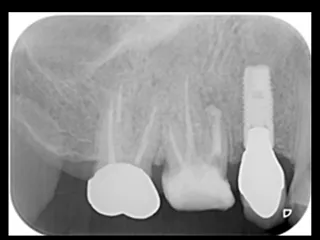

CASE No.1 奈良 嘉峰 先生(神奈川県茅ヶ崎市開業)

Labrida 施 術 前

施 術 前 (レントゲン写真)

Labrida 施 術 後(4週後 )

炎症とBOP消失

施 術 後 (レントゲン写真)